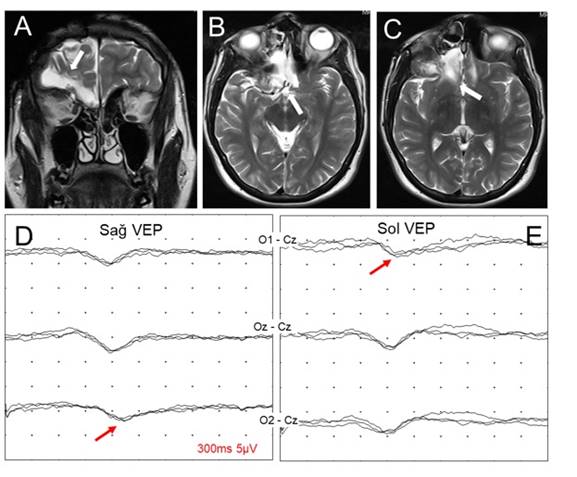

Şekil 6. Altı yıl önce trafik kazası sonucu

sağ orbita tavanında fraktür

ve kiazma optikuma bası

nedeniyle opere olan 20 yaşındaki erkek hastanın koronal (A) ve aksiyal (B,

C) planda T2 MR kesitleri ve patern VEP

incelemesi (D, E). Sağ göz uyarımıyla sağ

(O2-Cz), sol göz uyarımıyla sol (O1-Cz) oksipital

bağlantılarından kaydedilen P100 latansının uzun

olduğu görülmektedir (çaprazlaşmış asimetri, kiazmatik

lezyon).